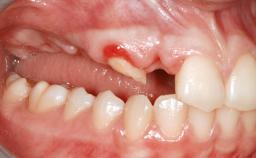

A 46-year-old woman was referred for treatment whose main complaints were mobility of her fixed partial dentures (right maxilla and left mandible) and periodontal bleeding during function. She also reported having taken systemic antibiotics to treat recurrent swelling in the area of the upper left molars. The patient had not seen a dentist for at least 2 years. She did not smoke and had no history of major systemic disease other than two minor orthopedic procedures some years back. The first-visit examination revealed poor plaque control, tooth mobility, periodontal disease, and a residual dentition widely associated with deep periodontal pockets.

Bone Volume Horizontally and vertically sufficient Horizontally deficient Deficient vertically or deficient vertically AND horizontally

Bone Volume Deficient vertically or deficient vertically AND horizontally